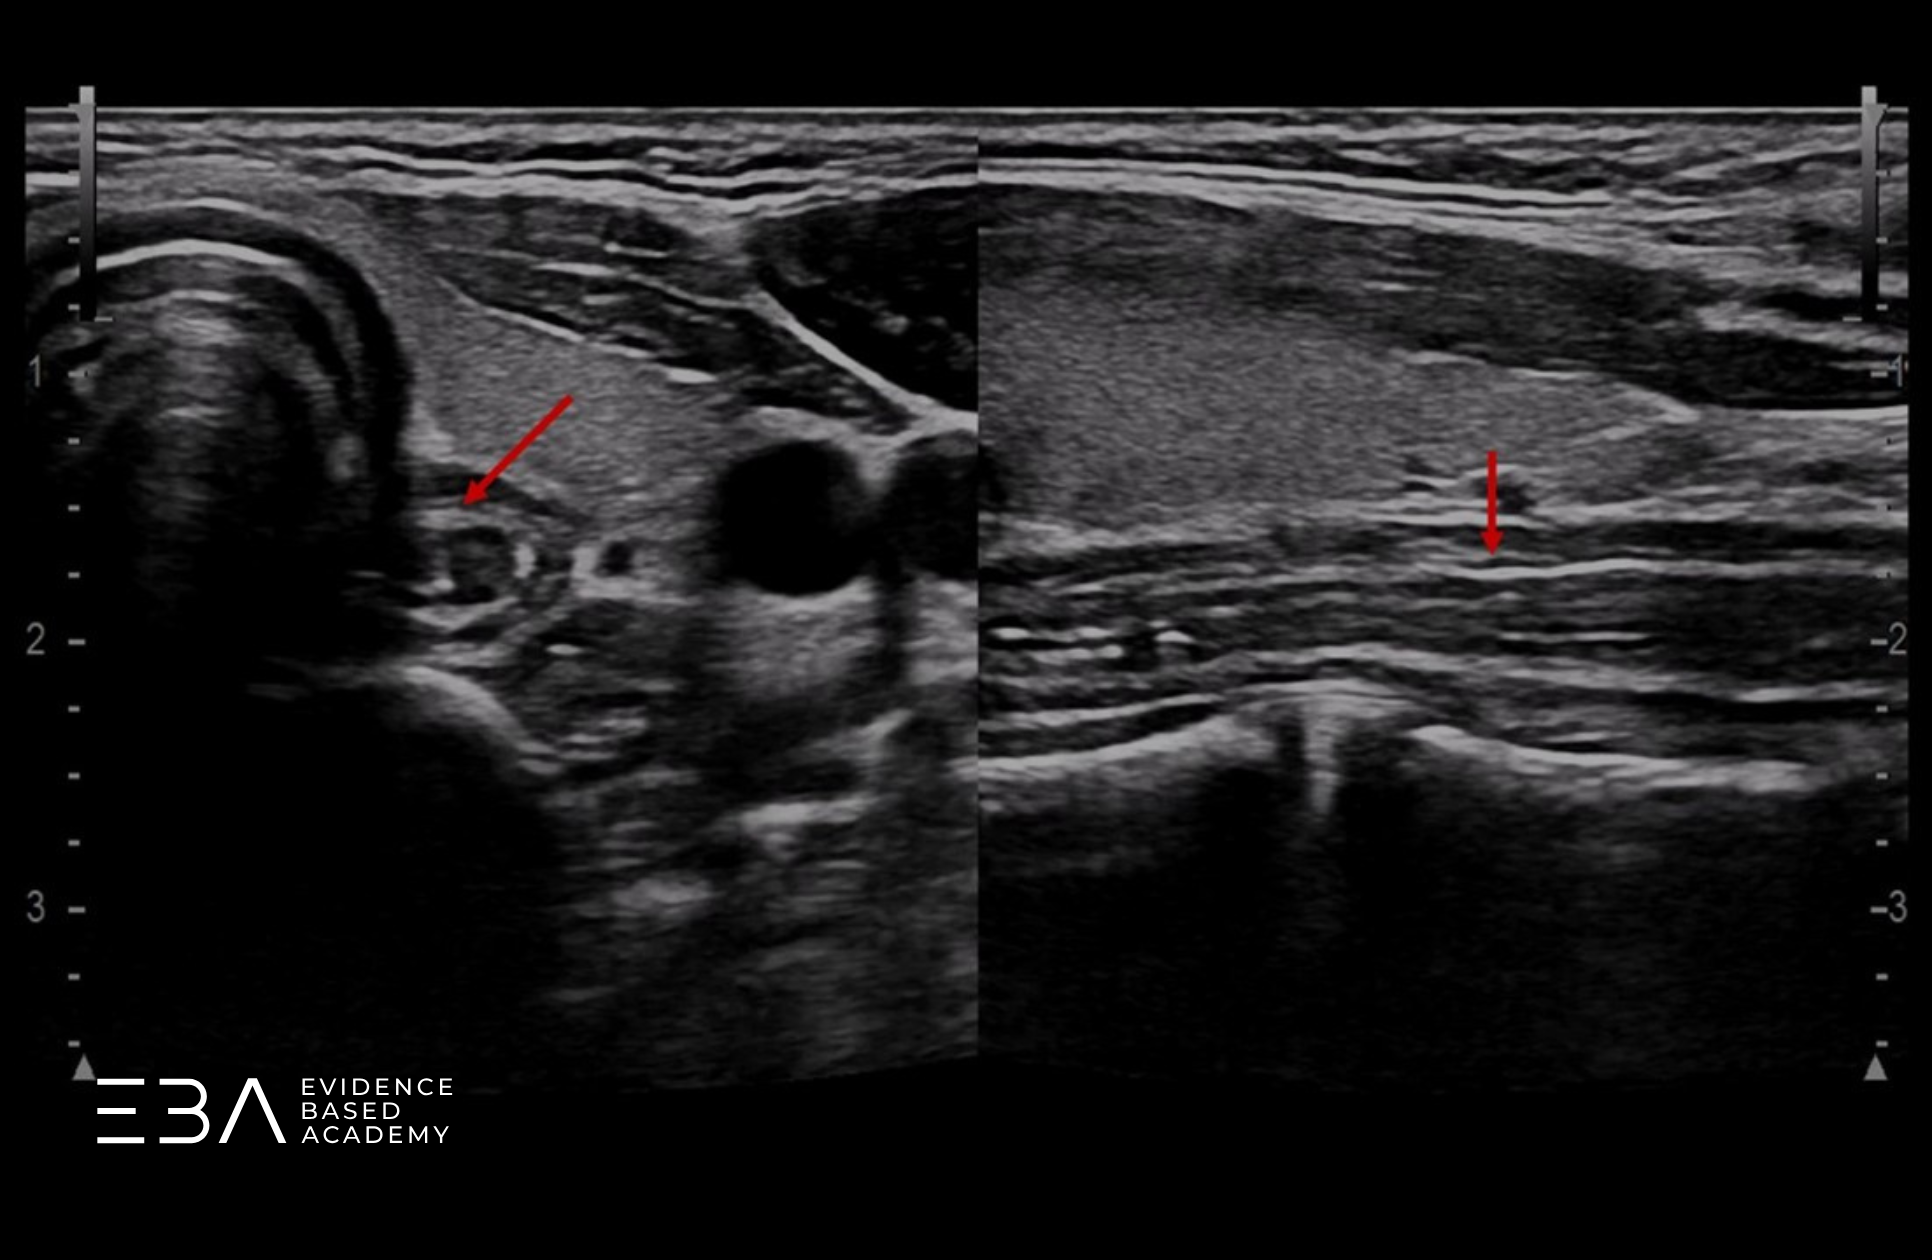

Porównanie prawidłowego przepływu (po prawej) i wzmożonego (po lewej).